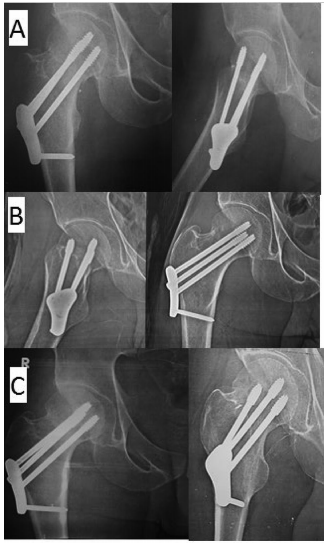

影像学结果:FNLP组的骨折愈合速度明显更快(15.2周 vs 20.6周),证实了其生物力学稳定性优势。图3展示的系列X线片清晰呈现了FNLP固定后的愈合进程。